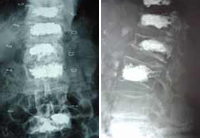

Cifoplastia_05Mujer, 55 años. Fractura aplastamiento derecho de L2 . Cifoplastia_03

Cifoplastia con balón. Fractura aplastamiento DX y DXI

Cifoplastia de L2